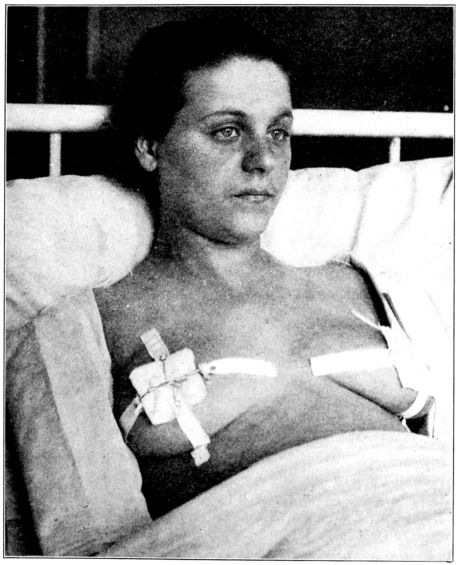

| 119. | Method of covering nipples with sterile gauze | 339 |

| 123. | Ice caps applied to engorged breasts | 344 |